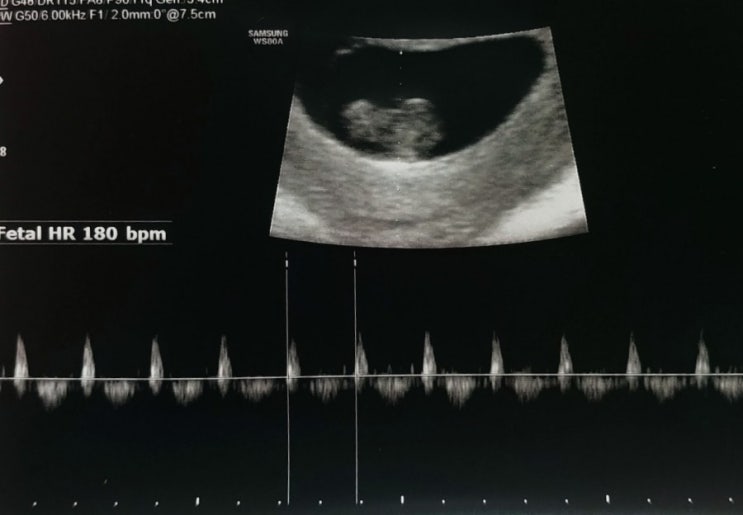

임신 8주차 기록

으아아아엌ㅋㅋ 울애기 심장뛰는거 보소! 드디어 이번주부터 남편이랑 촘파실 같이 들어가서 봤당ㅋㅋ 양정...